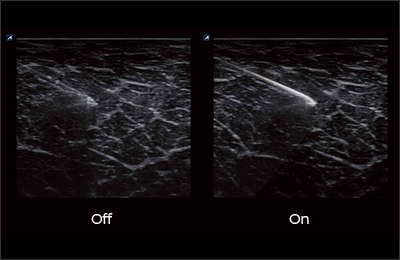

L8-17H

High density linear transducer(8-17MHz)

Application:

Breast, EM, MSK, Vascular, Small Parts

L3-12H

High density linear transducer (3-12MHz)

Application:

Breast, EM, MSK, Vascular, Small Parts

L3-12HWD

High density wide footprint linear transducer (3-12MHz)

Application:

Breast, EM, MSK, Vascular, Small Parts, Appendix

L3-12T

Linear transducer (3-12MHz)

Application:

Breast, EM, MSK, Vascular, Small Parts, Appendix